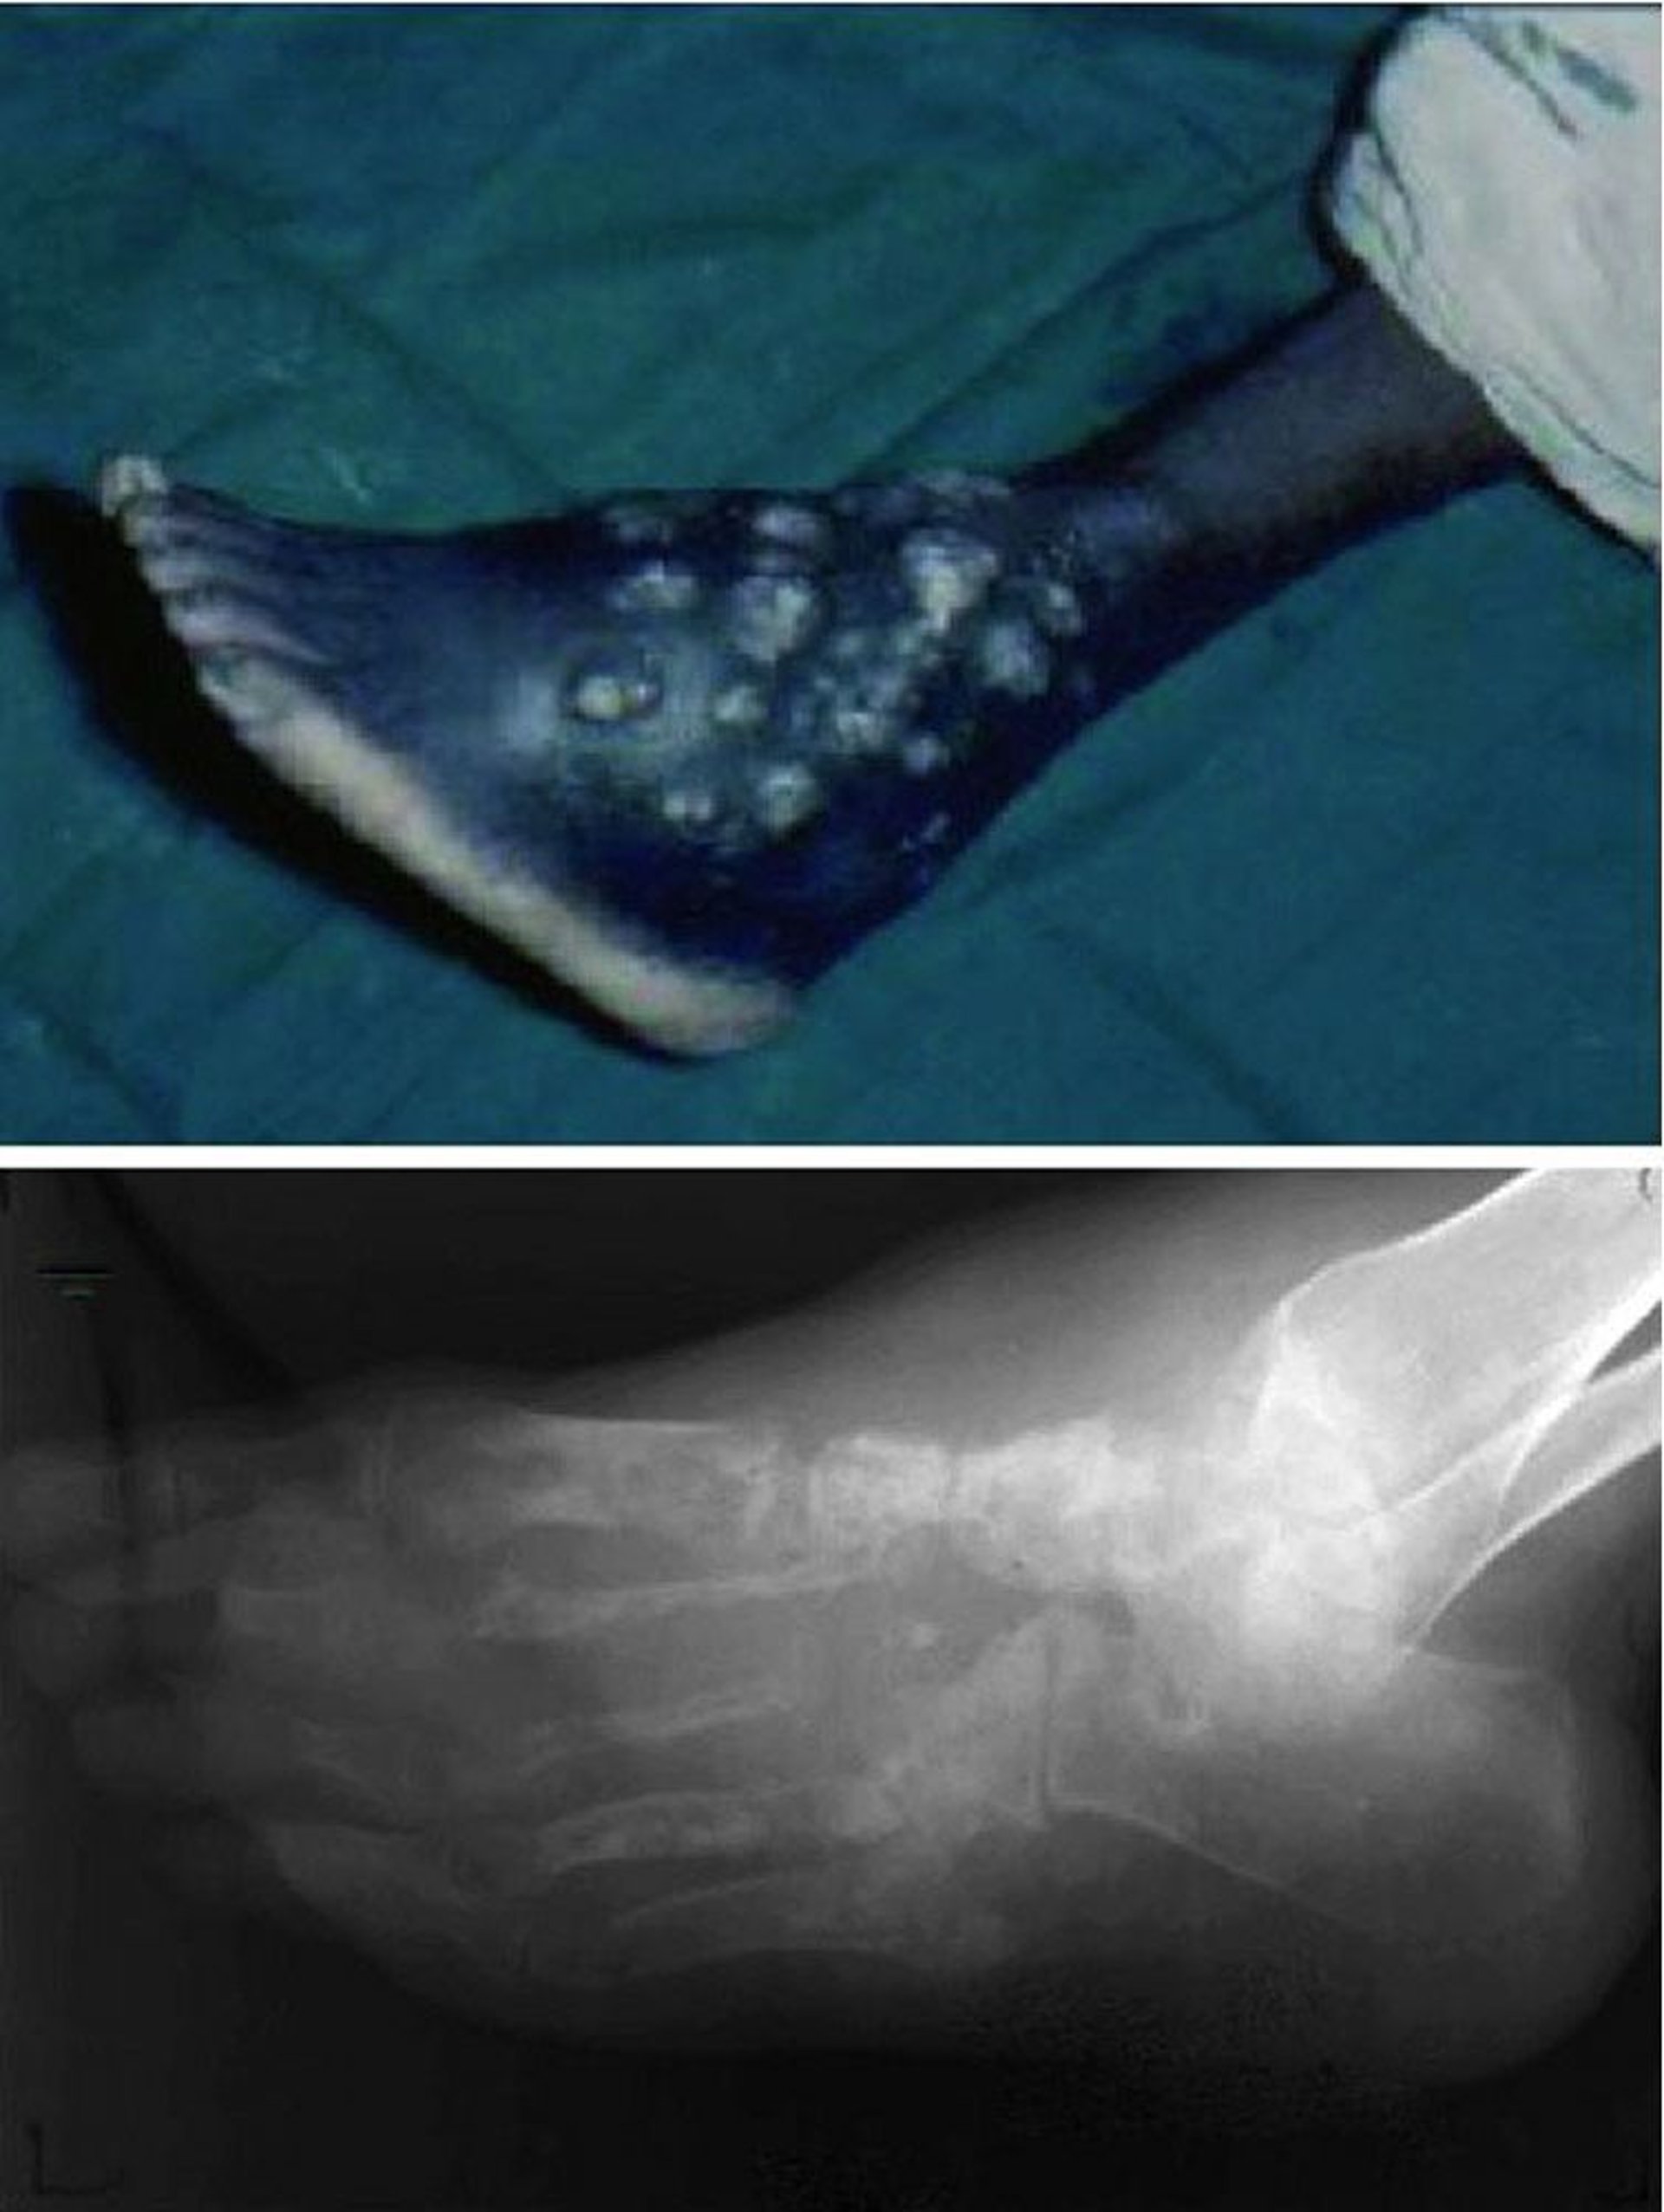

この写真には,治癒しない慢性創傷が写っており,排膿および潰瘍が繰り返しみられ(上),足の骨構造の全体にわたり破壊が進行している(下)。